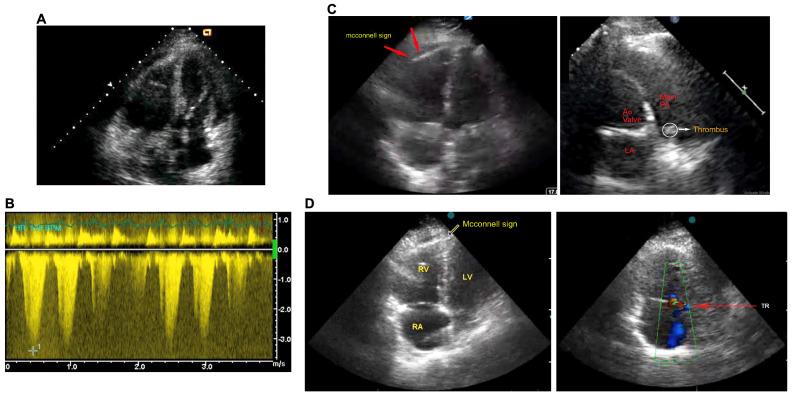

Snakebite envenoming and its resulting complications are serious threats to the health of vulnerable people living in rural areas of developing countries. The knowledge of the heterogeneity of symptoms associated with snakebite envenoming and their management strategies is vital to treat such life-threatening complications to save lives. Russell's viper envenomation induces a diverse range of clinical manifestations from commonly recognised haemotoxic and local effects to several rare conditions that are often not reported. The lack of awareness about these unusual manifestations can affect prompt diagnosis, appropriate therapeutic approaches, and positive outcomes for patients. Here, we report pulmonary thromboembolism that developed in three patients following Russell's viper envenomation and demonstrate their common clinical features and diagnostic and therapeutic approaches used. All patients showed clinical signs of local (oedema) and systemic (blood coagulation disturbances) envenomation, which were treated using polyvalent antivenom. They exhibited elevated heart rates, breathlessness, and reduced oxygen saturation, which are non-specific but core parameters in the diagnosis of pulmonary embolism. The recognition of pulmonary embolism was also achieved by an electrocardiogram, which showed sinus tachycardia and computed tomography and echocardiogram scans further confirmed this condition. Anti-coagulant treatment using low-molecular-weight heparin offered clinical benefits in these patients. In summary, this report reinforces the broad spectrum of previously unreported consequences of Russell's viper envenomation. The constant updating of healthcare professionals and the dissemination of major lessons learned in the clinical management of snakebite envenoming through scientific documentation and educational programs are necessary to mitigate the adverse impacts of venomous snakebites in vulnerable communities.